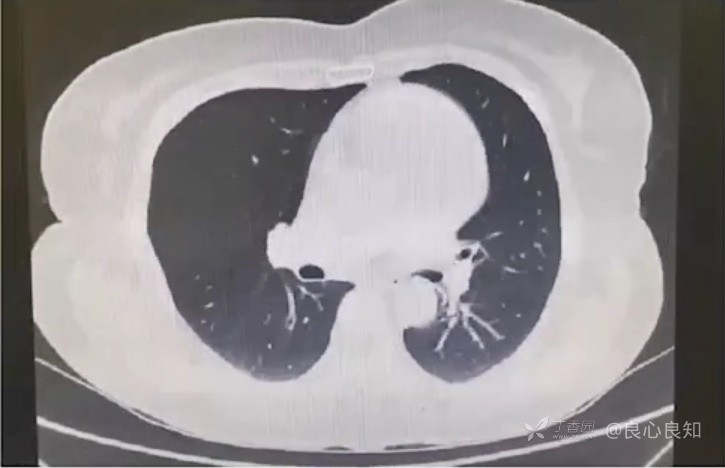

胸部CT:肺内少许索条及膨胀不全,主动脉瓣环少许钙化,微量心包积液可能。